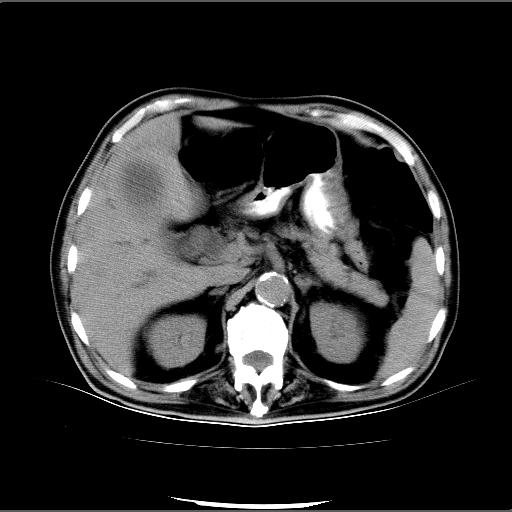

患者男82岁,黄染,发热10天,无腹痛。

1胆总管下端结石伴肝内外胆管扩张;2胆囊颈部结石伴胆囊积液

胆囊多发结石,胆囊积液;胆总管中下段结石,中上段扩张。

胆总管下段结石伴胆道系统扩张;胆囊炎伴胆囊结石.

有时胆总管下段结石的密度并不是均匀的高密度,而是以高密度为主的伴中心等密度的混合物,这与胆道结石的多样性有关,少数时候诊断困难时应结合临床病史,症状等,还有增强扫描都可以帮助明确诊断!!常与胆道蛔虫伴钙化鉴别!

1、胆总管壶腹部结石并胆总管、胆囊及肝内胆管扩张。2、胆囊多发结石。3、两下胸膜局限性增厚。4、胃体部大弯侧胃壁稍厚,建议:多量饮水后增强ct扫描除外占位性病变。

此病例有结果了:患者术后为:胆总管下段结石伴胆道系统扩张;胆囊炎伴胆囊结石。

各位战友分析的都很正确,是一个典型的病例。